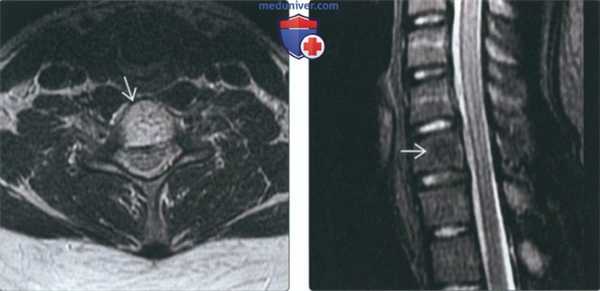

(Слева) На аксиальной МРТ (Т1 ВИ) определяются признаки агрессивной гемангиомы грудного позвонка с распространением в задние отделы и эпидуральное пространство. Жир визуализируется лишь в одной области. Точечный рисунок обусловлен трабекулами в гемангиоме.

(Справа) На сагиттальной МРТ (Т2 ВИ) визуализируется агрессивная гемангиома с гиперинтенсивным сигналом и легко различимым крупным эпидуральным компонентом. Видны также другие гемангиомы.